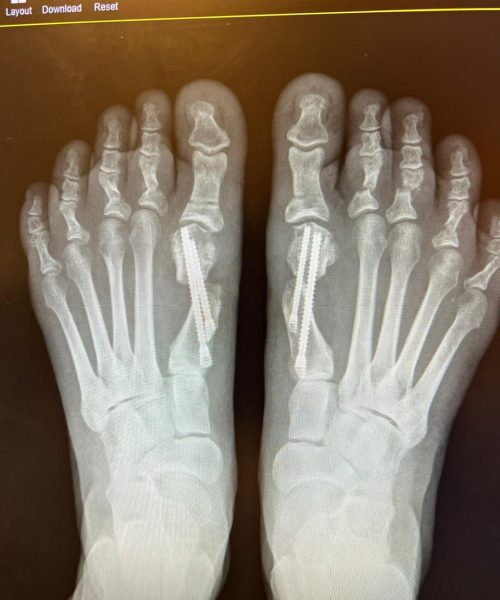

O que é a Cirurgia de Joanete Percutânea

A cirurgia de joanete percutânea é uma técnica que trata joanetes por meio de pequenas incisões e instrumentos especializados, buscando corrigir a deformidade do dedo do pé.